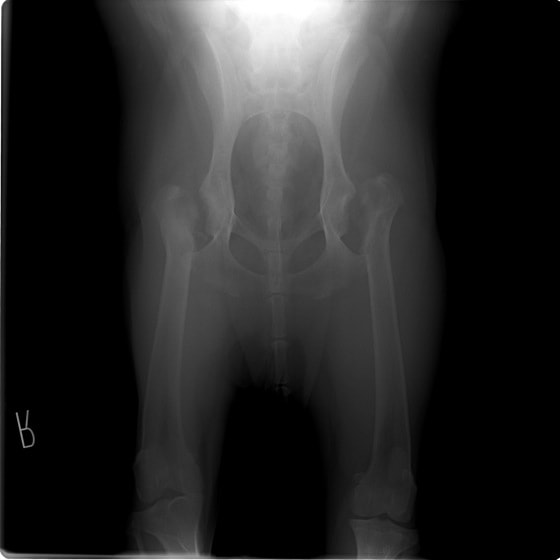

重度股関節形成不全の症例

THR法を実施した症例のレントゲン写真